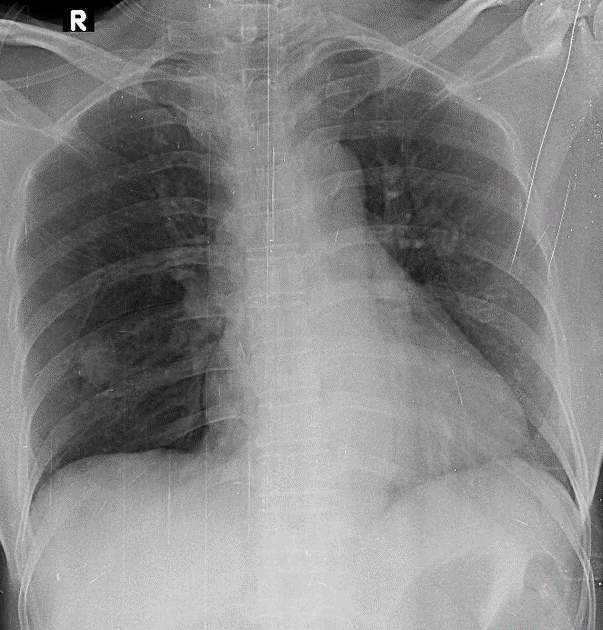

Hãy phân tích tình huống Nữ 61 tuổi

1-Nốt mờ thùy dưới phổi (P) => Khả năng u phổi 2-Bóng tim to